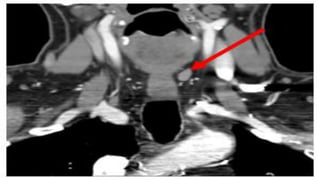

Pre-op TUMORS localization-

PRE-OP TUMOR LOALIZATION.

• Ultrasonography

• MRI

• CT

• Tl 201 – Tc99m scan

• 15.

Pre-op TUMORS localization- PRE-OPTUMOR LOALIZATION. • Ultrasonography • MRI • CT • Tl 201 – Tc99m scan